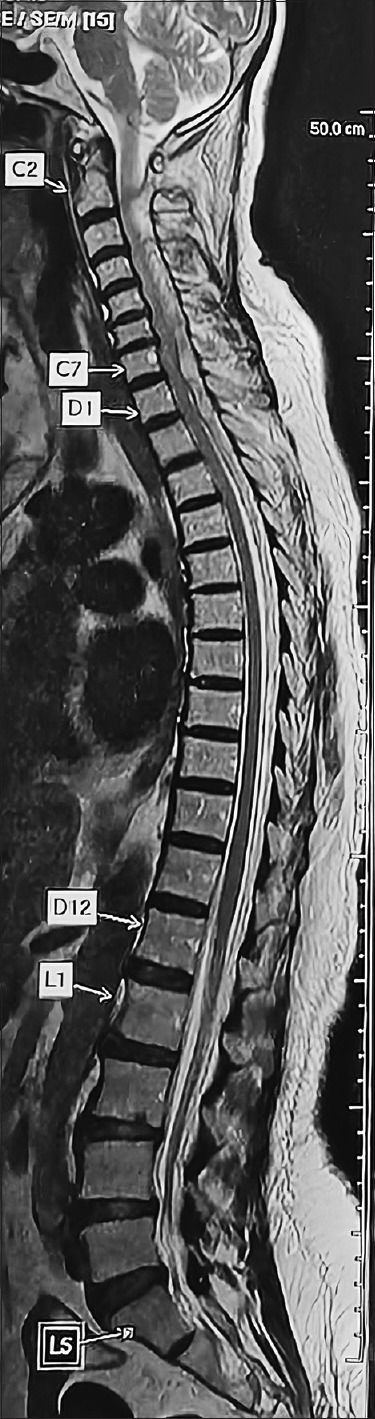

溶栓治疗后的灾难性自发性脊柱硬膜外血肿(SSEH)是神经外科和心脏病学的复杂交叉难题。本病例报告介绍了一名 66 岁女性在注射链激酶溶栓治疗下壁心肌梗死后迅速发生压迫性脊髓病的病例。SSEH 虽然罕见,但由于其可能导致永久性神经损伤和死亡,因此需要及时识别。讨论强调了 SSEH 的临床意义、解剖学考虑因素以及准确诊断和有效处理 SSEH 所需的多学科方法。结论强调了临床医生,尤其是实施溶栓疗法的心脏病专家,在溶栓后出现神经功能缺损的患者中考虑 SSEH 的必要性。

Catastrophic spontaneous spinal epidural hematoma (SSEH) following thrombolysis poses a complex intersection of neurosurgical and cardiological challenges. This case report presents the institutional experience of a 66-year-old female who developed rapid-onset compressive myelopathy after thrombolysis for inferior wall myocardial infarction with injection streptokinase. SSEH, although rare, demands prompt recognition due to its potential for permanent neurologic injury and mortality. The discussion highlights the clinical significance, anatomical considerations, and multidisciplinary approach requisite for accurate diagnosis and effective management of SSEH. The conclusion underscores the necessity for clinicians, particularly cardiologists administering thrombolytic therapies, to consider SSEH in postthrombolysis patients presenting with neurological deficits.